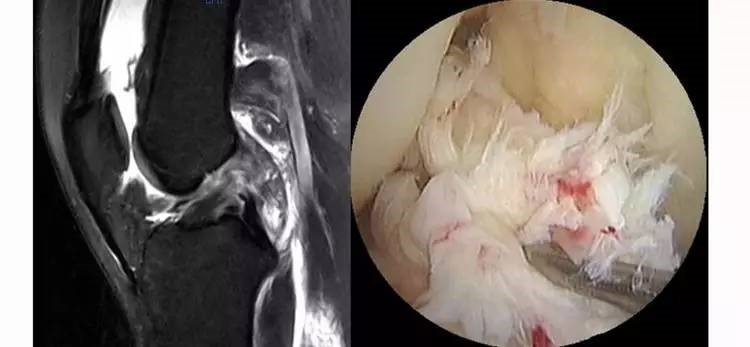

ACL的正常MRI表现——

1.各序列均为低信号。

2.韧带平直,边界清楚,有较好的张力。

3.韧带内可有脂肪及滑膜条纹影。